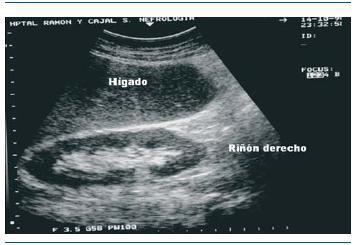

La Ecografía o Ultrasonografía tiene un rol muy importante en la evaluación de los riñones. Si bien es cierto es un examen auxiliar y depende del observador, una examen bien realizado puede ayudarnos a enfocar de mejor manera el estado de nuestros riñones.

En primer lugar nos sirve para poder determinar la ubicación habitual de ambos riñones, pues se han visto casos que por un examen ecográfico de rutina se han identificado alteraciones como ausencia de un riñón, riñones en herradura, quise múltiples, etc. asimismo, nos sirve para determinar aproximadamente el tamaño de ambos riñones.

En tercer lugar, nos sirve para determinar el espesor y la ecogenicidad de la corteza o parenquima renal. el espesor normal es de 18 a 20 mm; a medida que la enfermedad renal progresa a estadíos mas avanzados la corteza se va adelgazando, teniendo valores de 10 a 12 mm cuando el riñón ya está en estadíos muy avanzados es decir, cuando ya esta presente una enfermedad renal crónica.